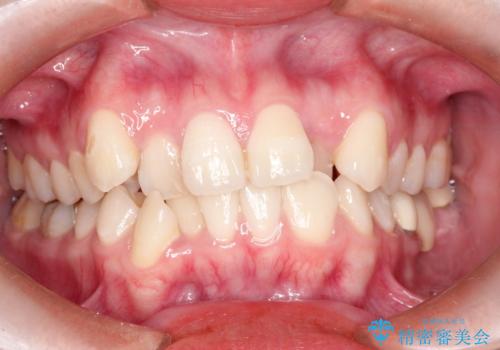

八重歯のワイヤーによる抜歯矯正 矯正治療と並行してセラミック治療も

- 八重歯と前歯のガタガタを主訴に来院されました。

左下の奥歯がすでに1本抜歯されており、ブリッジを装着されていました。

ブリッジを除去して、左下以外の上顎両側と右下の歯を合計3本抜歯して矯正する計画としました。